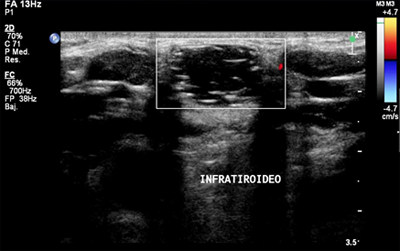

Se le realizó una analítica urgente donde se objetivó discreta leucocitosis con neutrofilia; y se solicitó valoración a ORL de guardia, quien realizó una fibroscopia dónde se observó una hipertrofia leve de base de lengua, resto sin hallazgos. Así mismo, también se solicitó una ecografía cervical ( Figura 1 y 2) que evidenciaba una lesión anecogénica con refuerzo sónico posterior en relación con su contenido quístico y un TAC cervical que nos mostraba una lesión con densidad líquida bien delimitada, unilocular, confirmándonos el diagnóstico de quiste del conducto tirogloso.

El diagnóstico es fundamentalmente clínico 2, las pruebas complementarias nos ayudarán a conocer las características del quiste y su relación con la glándula tiroides. Entre las pruebas complementarias destaca la ecografía cervical que lo detecta como una estructura anecoica, bien delimitada y con buena transmisión 8. La TAC cervical para algunos autores está indicada en todos los casos, pero para otros tiene las siguientes indicaciones: pacientes mayores 40 años, antecedentes de infección reciente, exploración clínica y/o sintomatología laríngea que sugiera malignización 3.

Figura 1.

Figura 2.